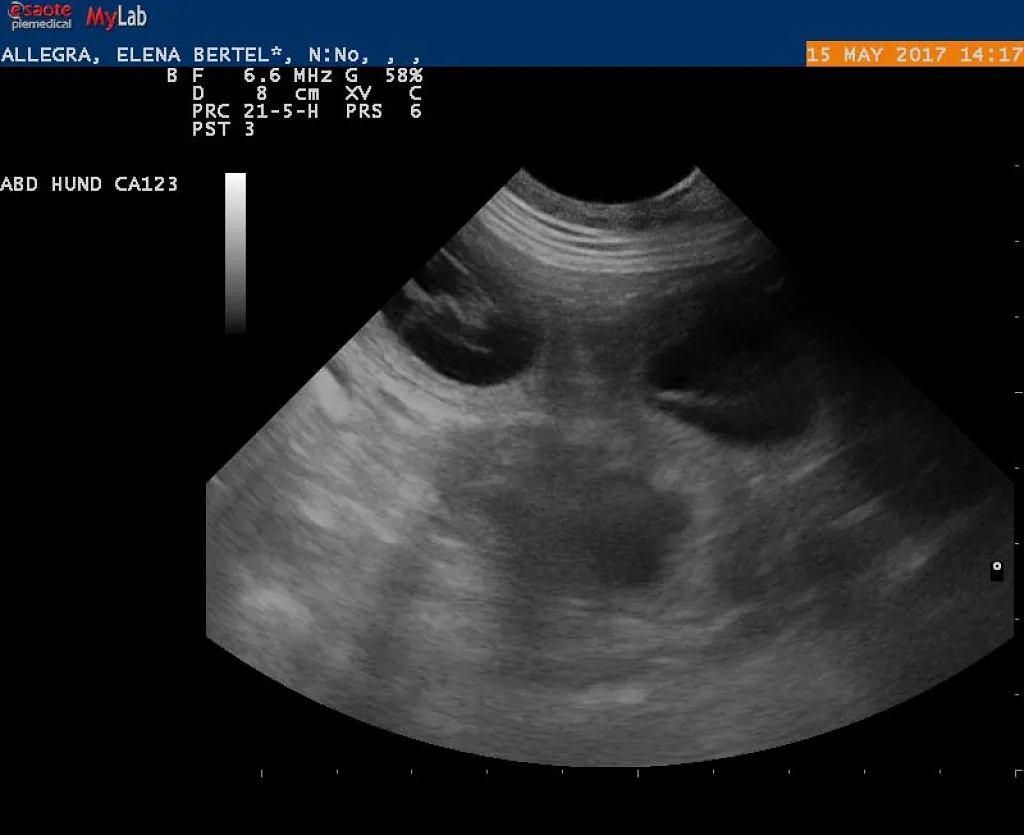

15.05.2017

Alice er drægtig!

e-kuld, 2017, sommer, kennel basta dog, schnauzere, schnauzerhvalpe, schnauzeropdræt, mellemschnauzer, alenzo, alice, hvalpe, købe schnauzer

Dejlig, dejlig nyhed!!!

Alice (Allegra)  er drægtig!

Scanning i dag har nemlig bekræftet den dejlige nyhed!

Hvor mange hvalpe er der inde? Tja, en del af dem kan du se på de billeder fra scanning :)

Nu krydser vi fingre for at alt går godt og vi får dejlige hvalpe efter de smukke og dygtige forældre!

P.S. Scaninngsbillederne ved klik på dem vil kunne ses i større størelse!